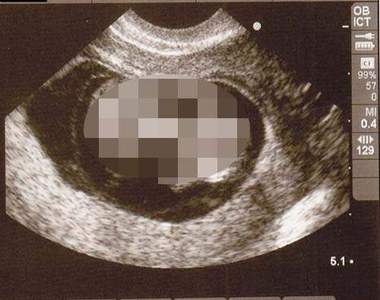

每位媽媽在懷寶寶的時候,都會定期去照超音波,看看寶寶的健康狀況。我還記得我之前陪我老姊去照超音波的時候,她看著動來動去的寶寶,整個感動到流下兩行淚,這時我就知道,我在我姊心中受疼愛的地位即將不保了 X...

人家常說,孩子是上帝派來凡間的小天使,但在小天使準備下凡到人世間的過程中,似乎沒有想像中的那麼像天使@_@``........最近有網友將網路上分享的超音波寶寶照做了總整理,雖然人家都說從超音波的照片...